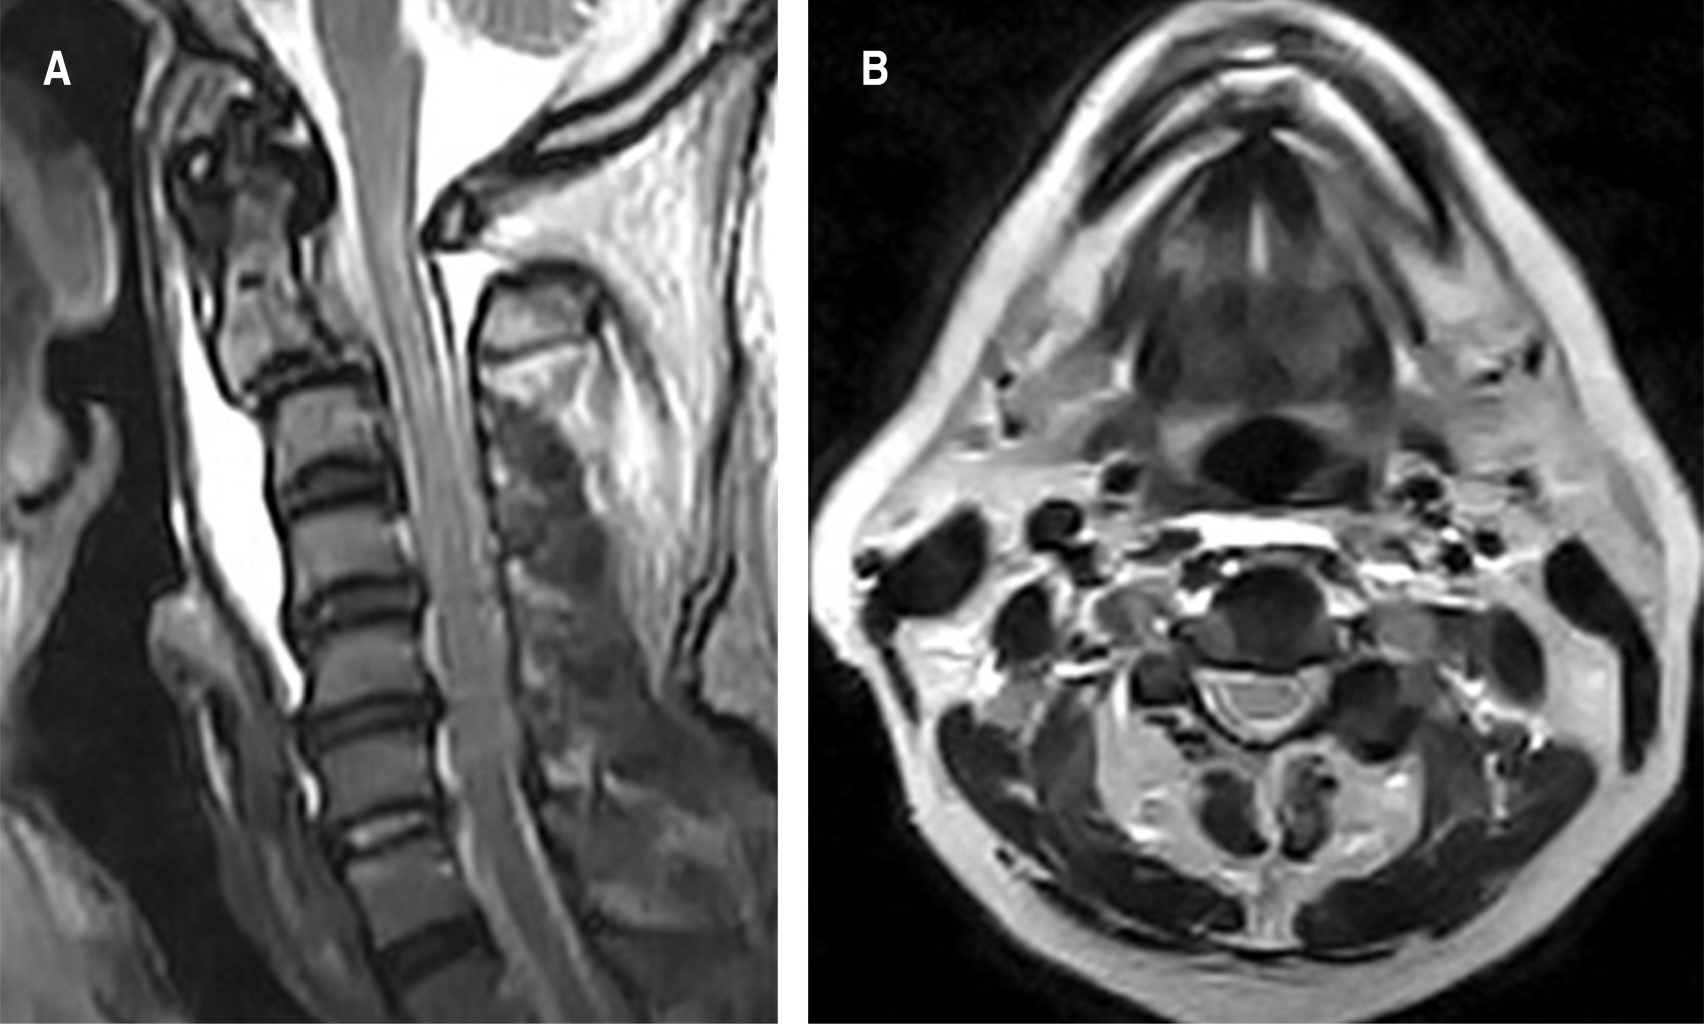

Fijación con tornillo transpedicular en C2 en el tratamiento de fractura de Hangman tipo III de Levine-Edwards: una opción para preservar el movimiento

Introducción: la fractura bilateral de la pars interarticularis de C2 por espondilolistesis traumática representa 4 a 7% de las fracturas cervicales y 20 a 22% de las fracturas de C2. La elección del abordaje quirúrgico sigue siendo controvertida; las opciones disponibles incluyen ACDF C2-C3, fusión posterior C2-C3, tornillo transpedicular de C2 solo y abordaje 360°. Presentación del caso: masculino, 60 años de edad, tras accidente automovilístico tipo volcadura, cursa con cervicalgia EVA 10/10, radiculopatía en C2-C5 derecha, fuerza 3/5 en escala MRC en C4-C5 derecho, reflejo bicipital derecho 1/+. TC con fractura de Hangman tipo III. Hicimos reducción cervical externa con apoyo de cabezal de Mayfield, abordaje cervical posterior y fijación trasnpedicular de C2, tornillos transmacizo facetario en C3 y barras laterales de titanio. Conclusions: las fracturas de Hangman tipo III deben diagnosticarse oportunamente debido al riesgo de lesión neurológica. Estas deben tratarse con fijación, si es posible con tornillo transpedicular en C2, que es una excelente opción para la reducción y estabilización de la fractura, mantenimiento de la alineación cervical y preservación de los rangos de movimiento.

Figura 1

Figura 2

Figura 3